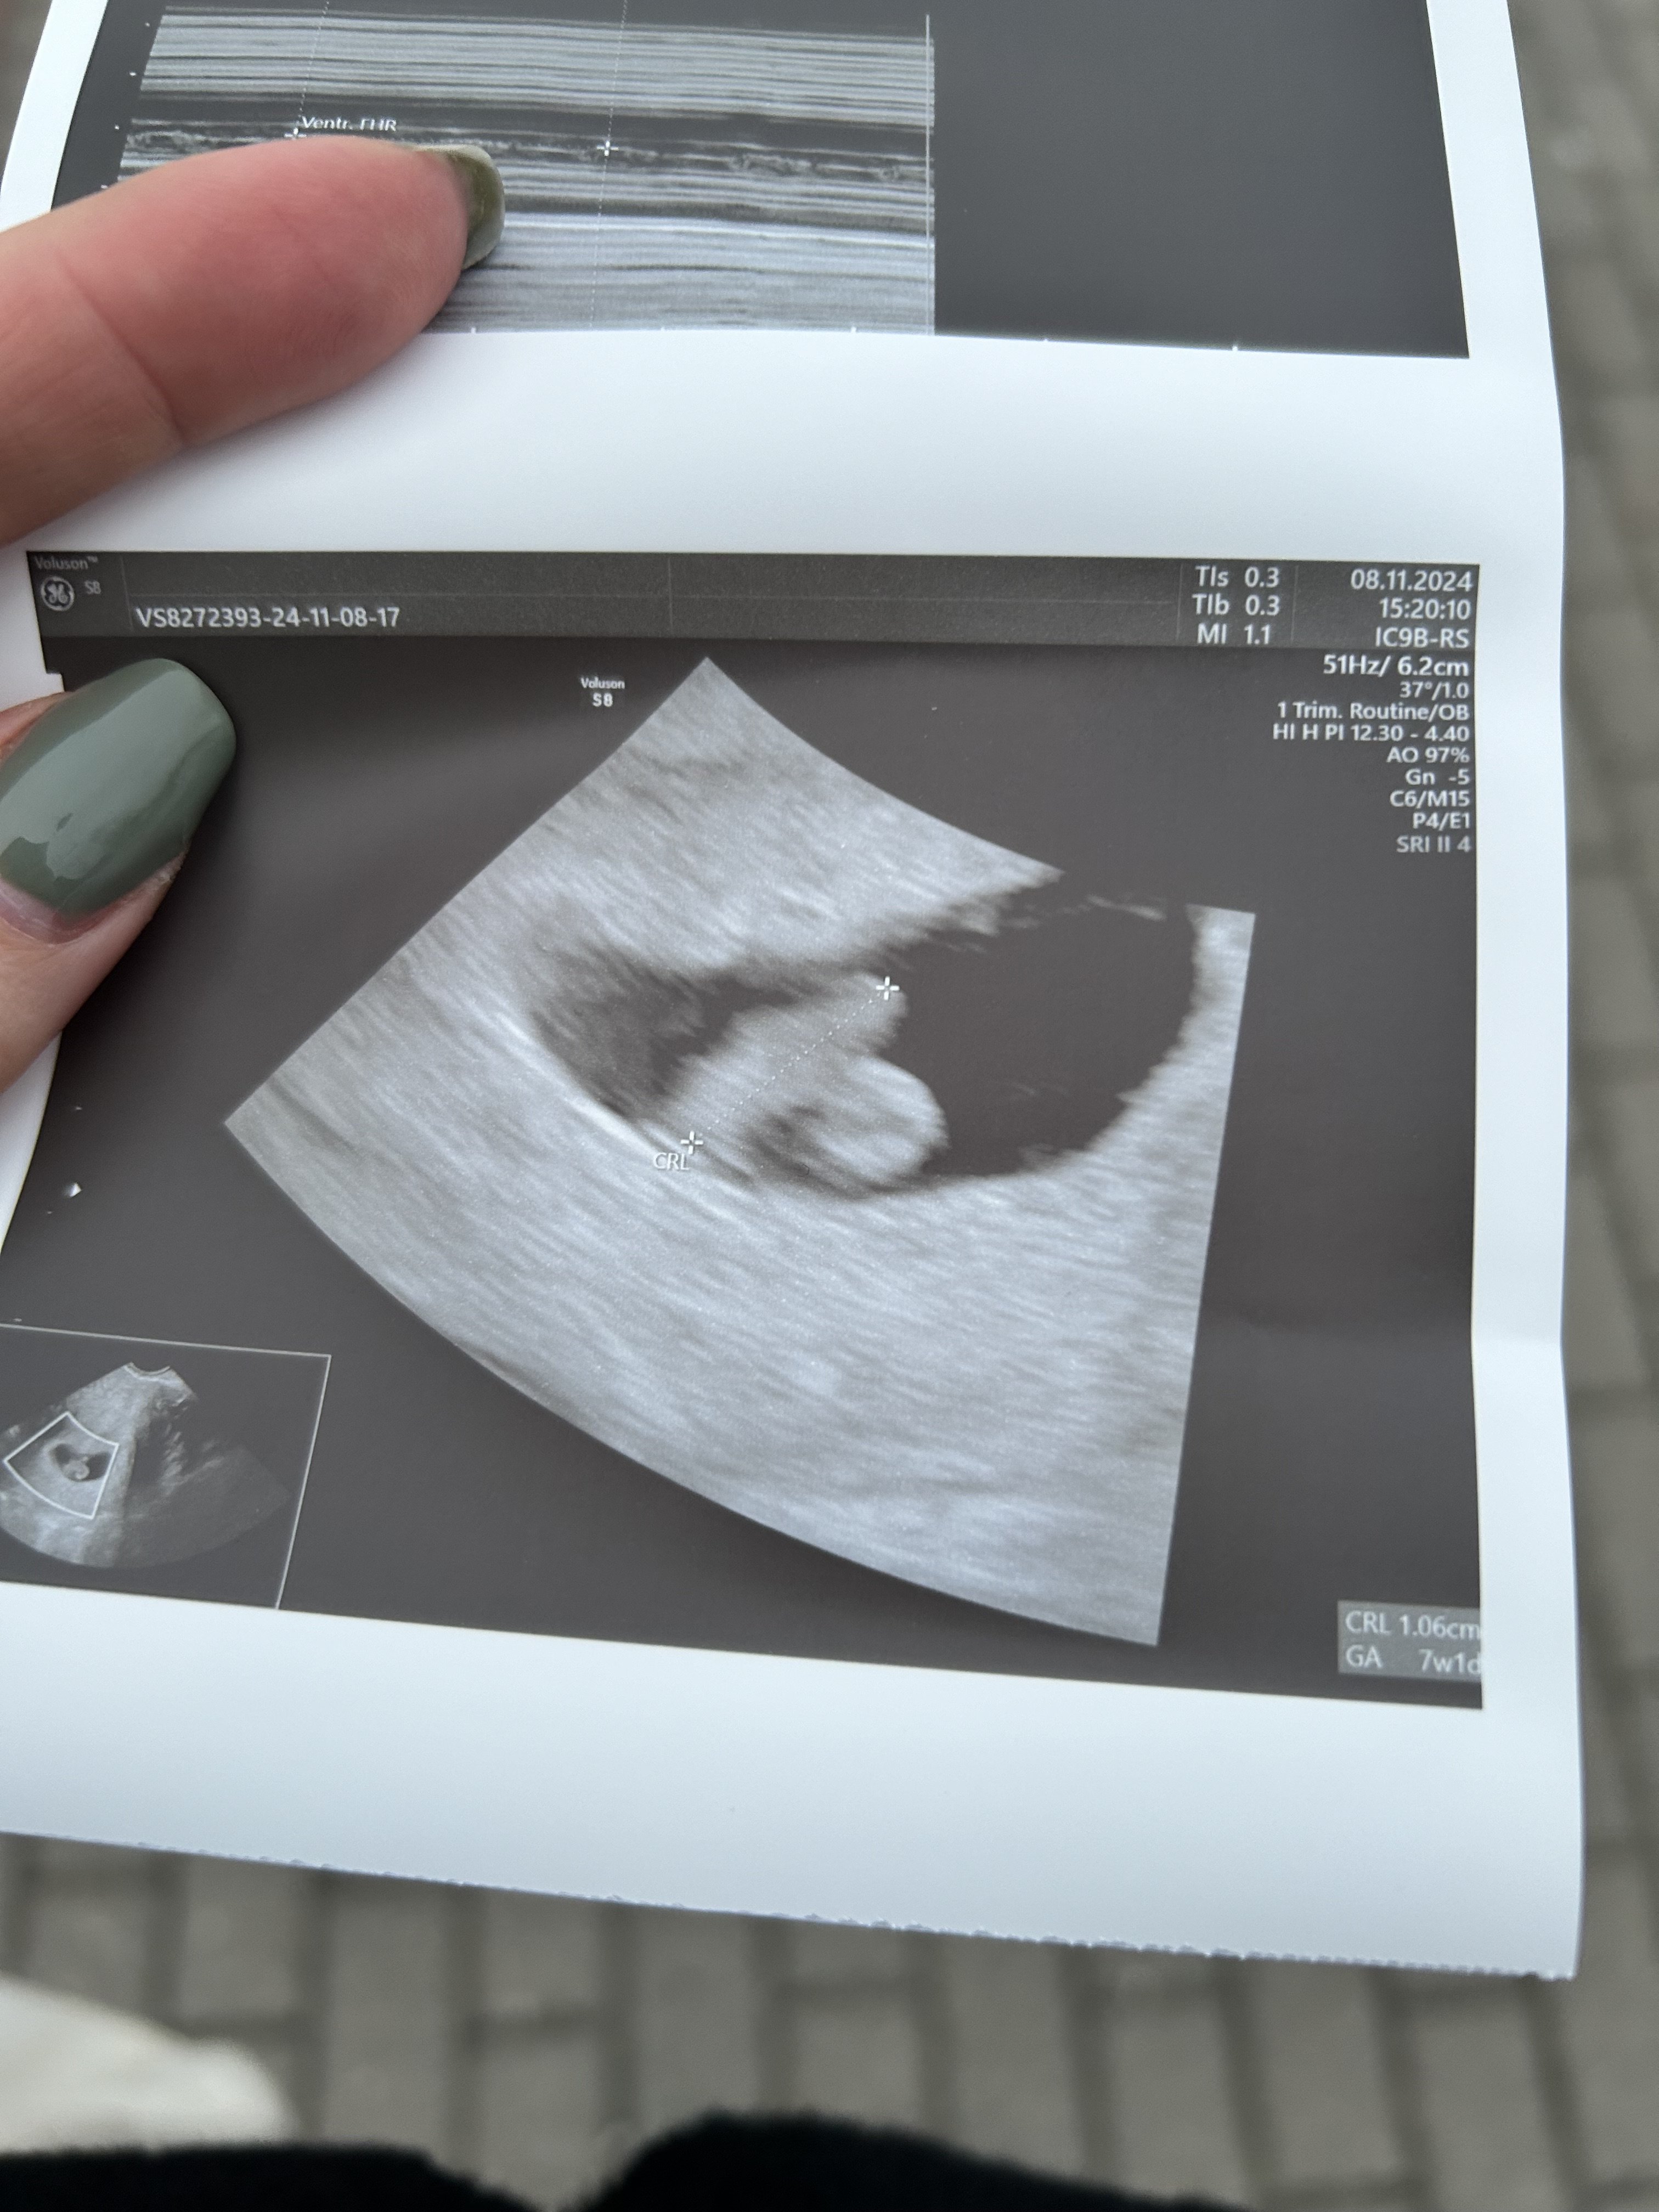

U mnie 1,1 cm dzidzi z pięknie bijącym serduszkiem♥️wg usg 7+1 (w poniedziałek 6+2, w srode 6+5, dzis 7+1..😳 zaraz się okaże że termin w maju😂)